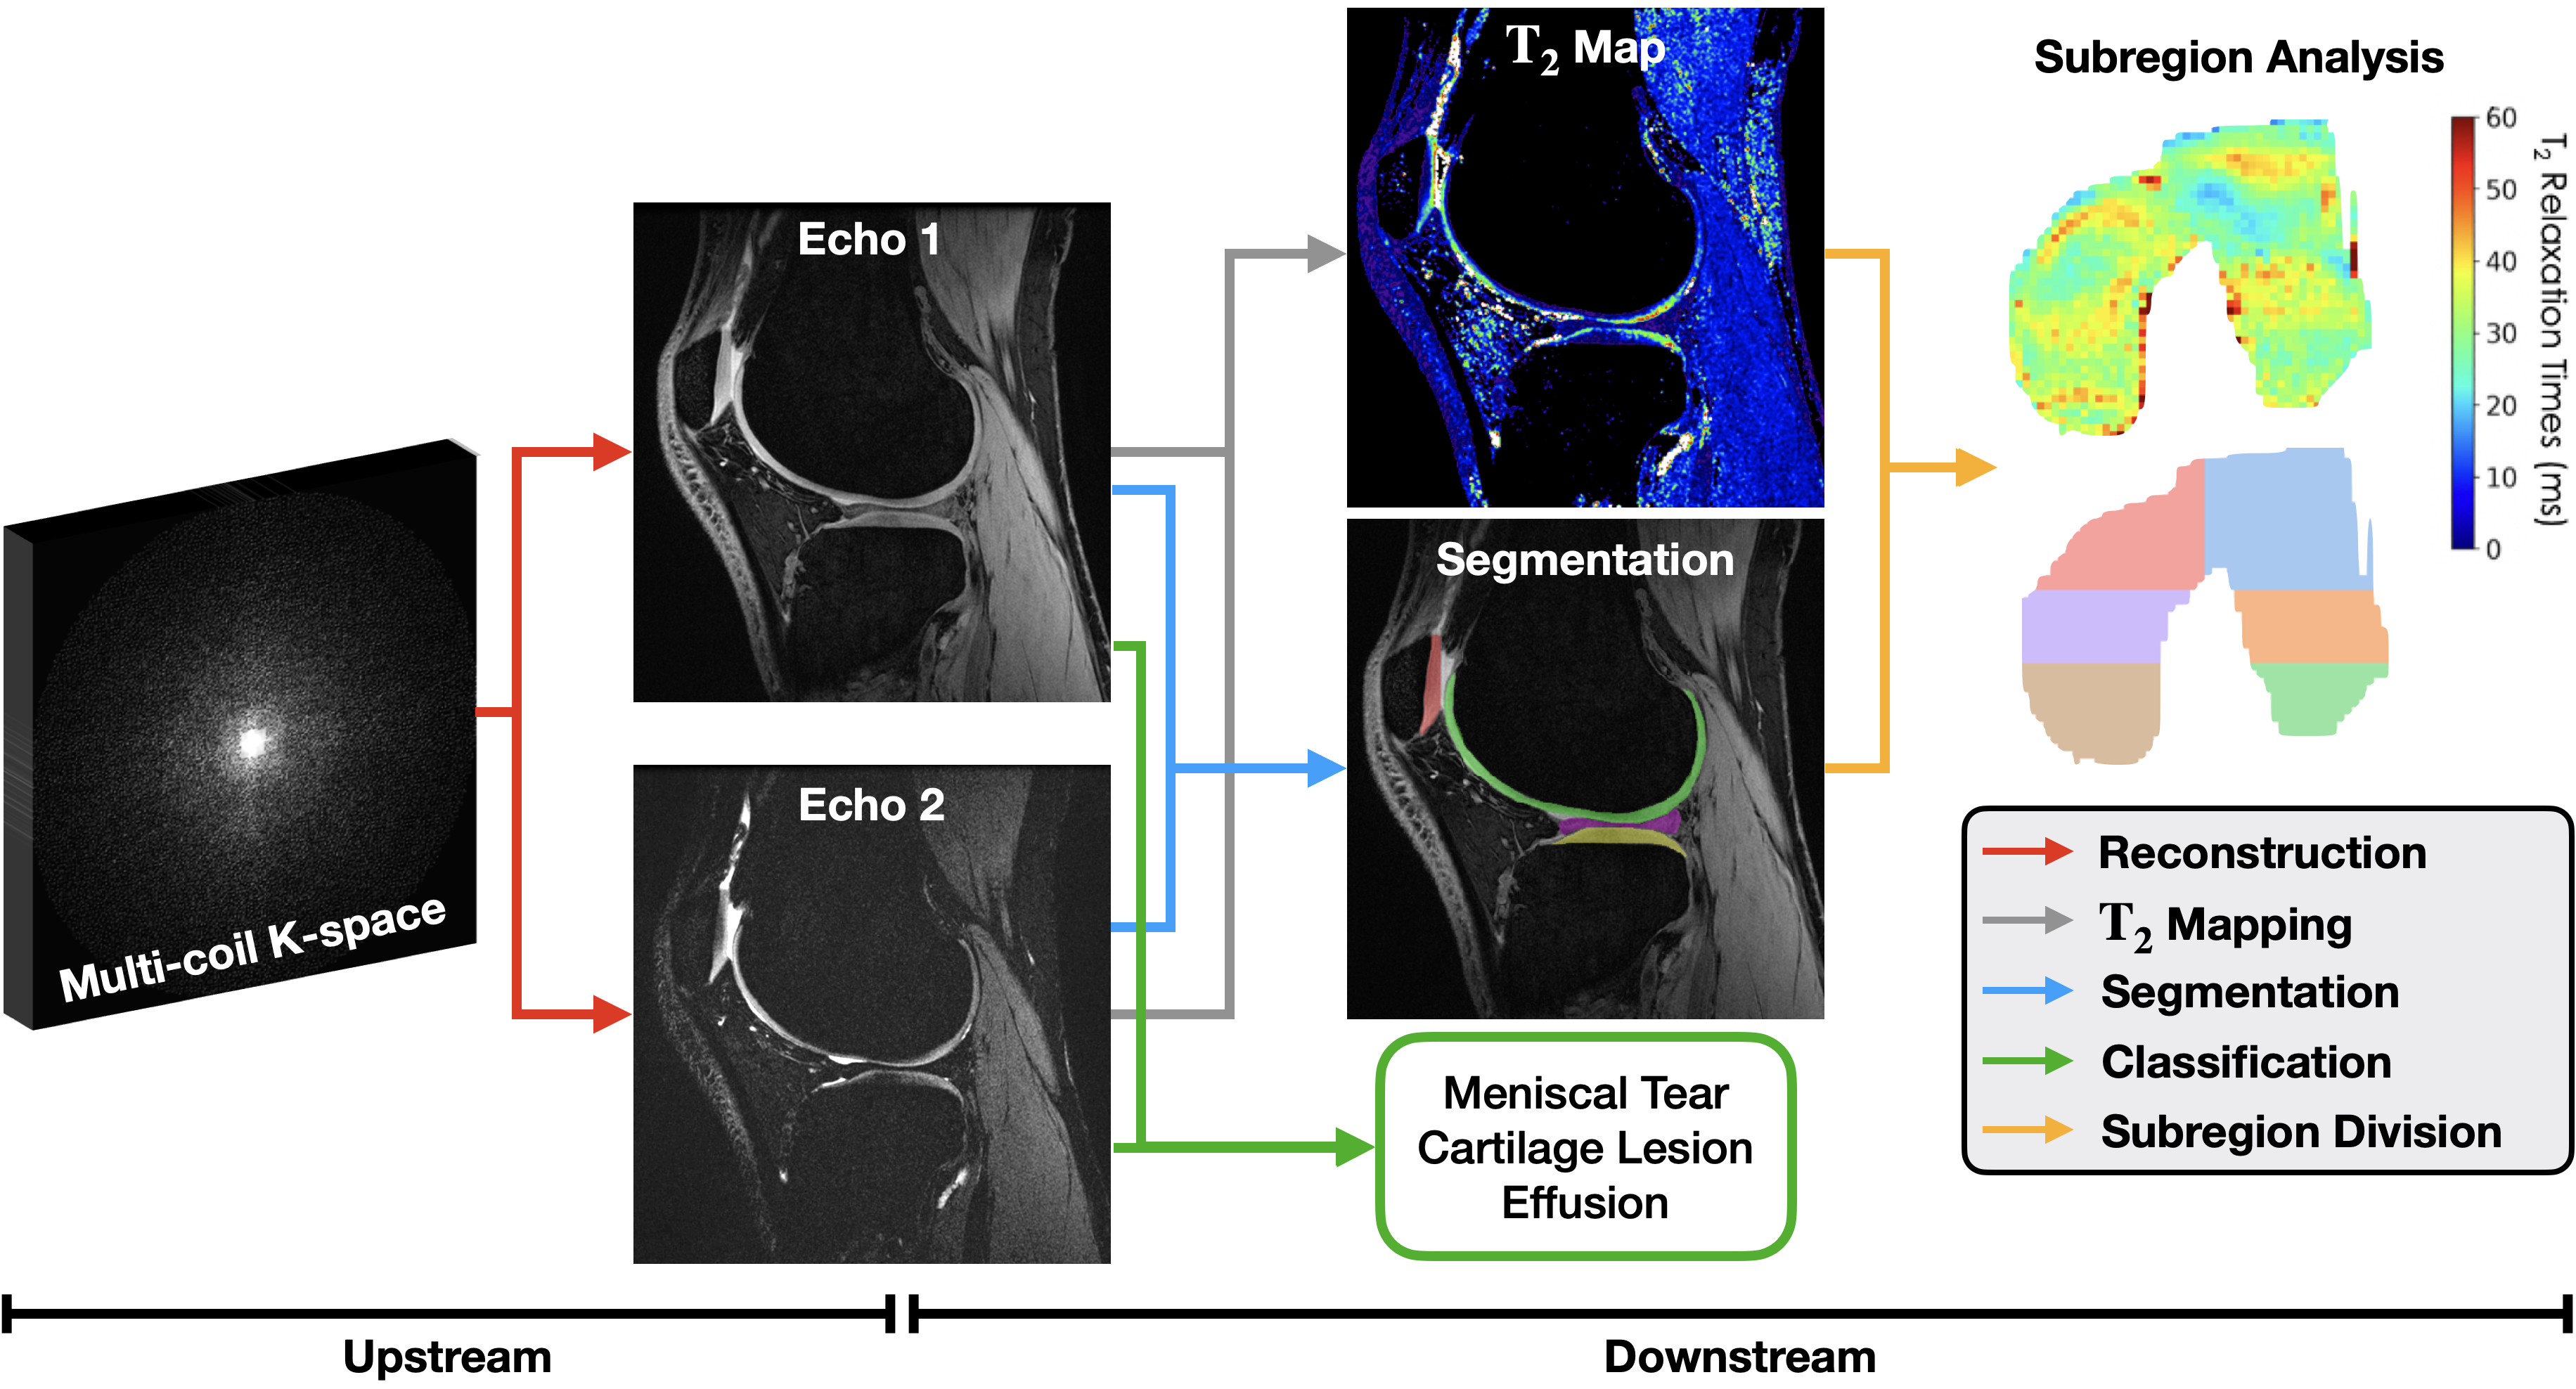

Assessing the impact of upstream reconstruction models on downstream image analysis: A workflow-centric evaluation

Ben Viggiano, Aashna Desai, Elka Rubin, and 7 more authors

Nov 2023